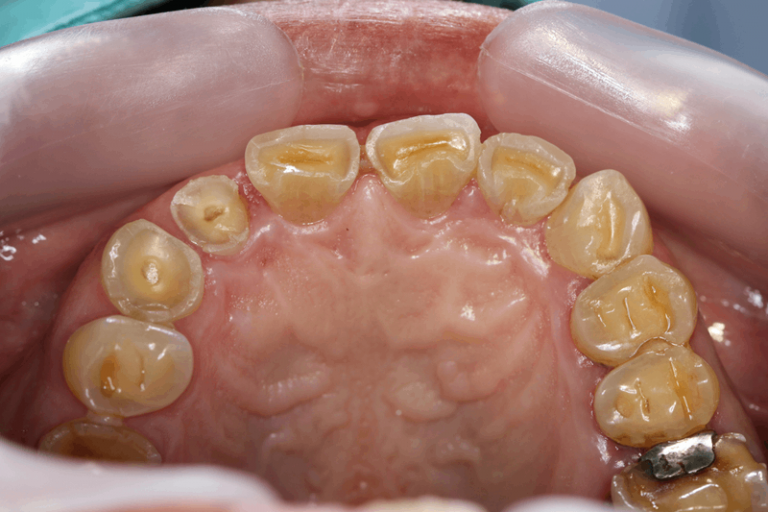

病患初期僅侵蝕琺瑯質時,可以沒有明顯的症狀,只有如牙齒帶黃色、牙齒表層有磨損現象、牙齒邊有破裂、牙齒看來「薄」了等。但當侵蝕到象牙質時,患者會感到牙齒酸軟。此外,在進食冷、熱甜點或酸性食物及飲品;刷牙或使用牙線時會感到刺痛。由於牙齒酸蝕症是慢性的,直到出現遇冷、熱、酸、甜,牙齒敏感症狀出現才會引起注意,而出現這種情況時,可能已經影響到牙齒的咀嚼功能。而且牙齒酸蝕造成的破壞是無法逆轉的,琺瑯質一旦流失就無法復原或再生。